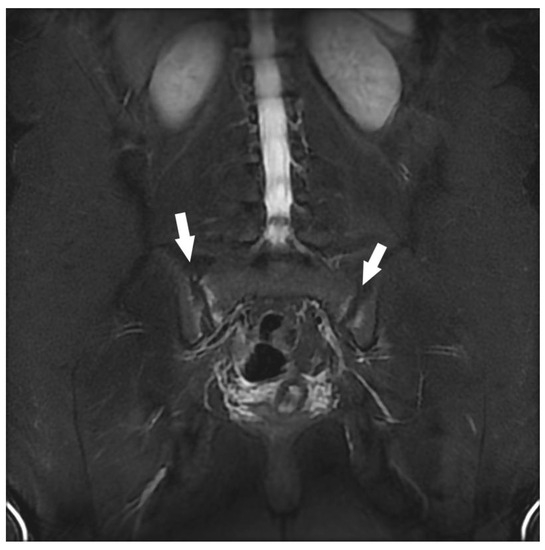

| Sacroiliac Joint | Congestive degenerative arthropathy | 10 |

| Inflammatory sacroiliitis | 4 | |

| Sacral fracture | 1 | |

| Congestive degenerative sacroiliac arthropathy 2 | 8 | |